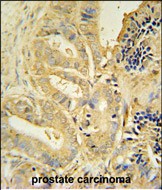

IHC 1/100-1/500 Human,Mouse,Rat